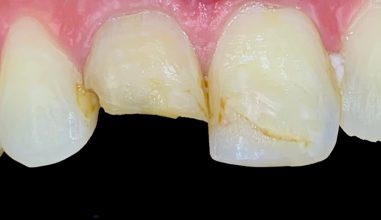

Learn MoreWe can help also produce the smile you’ve been dreaming by developing a treatment plan for you.